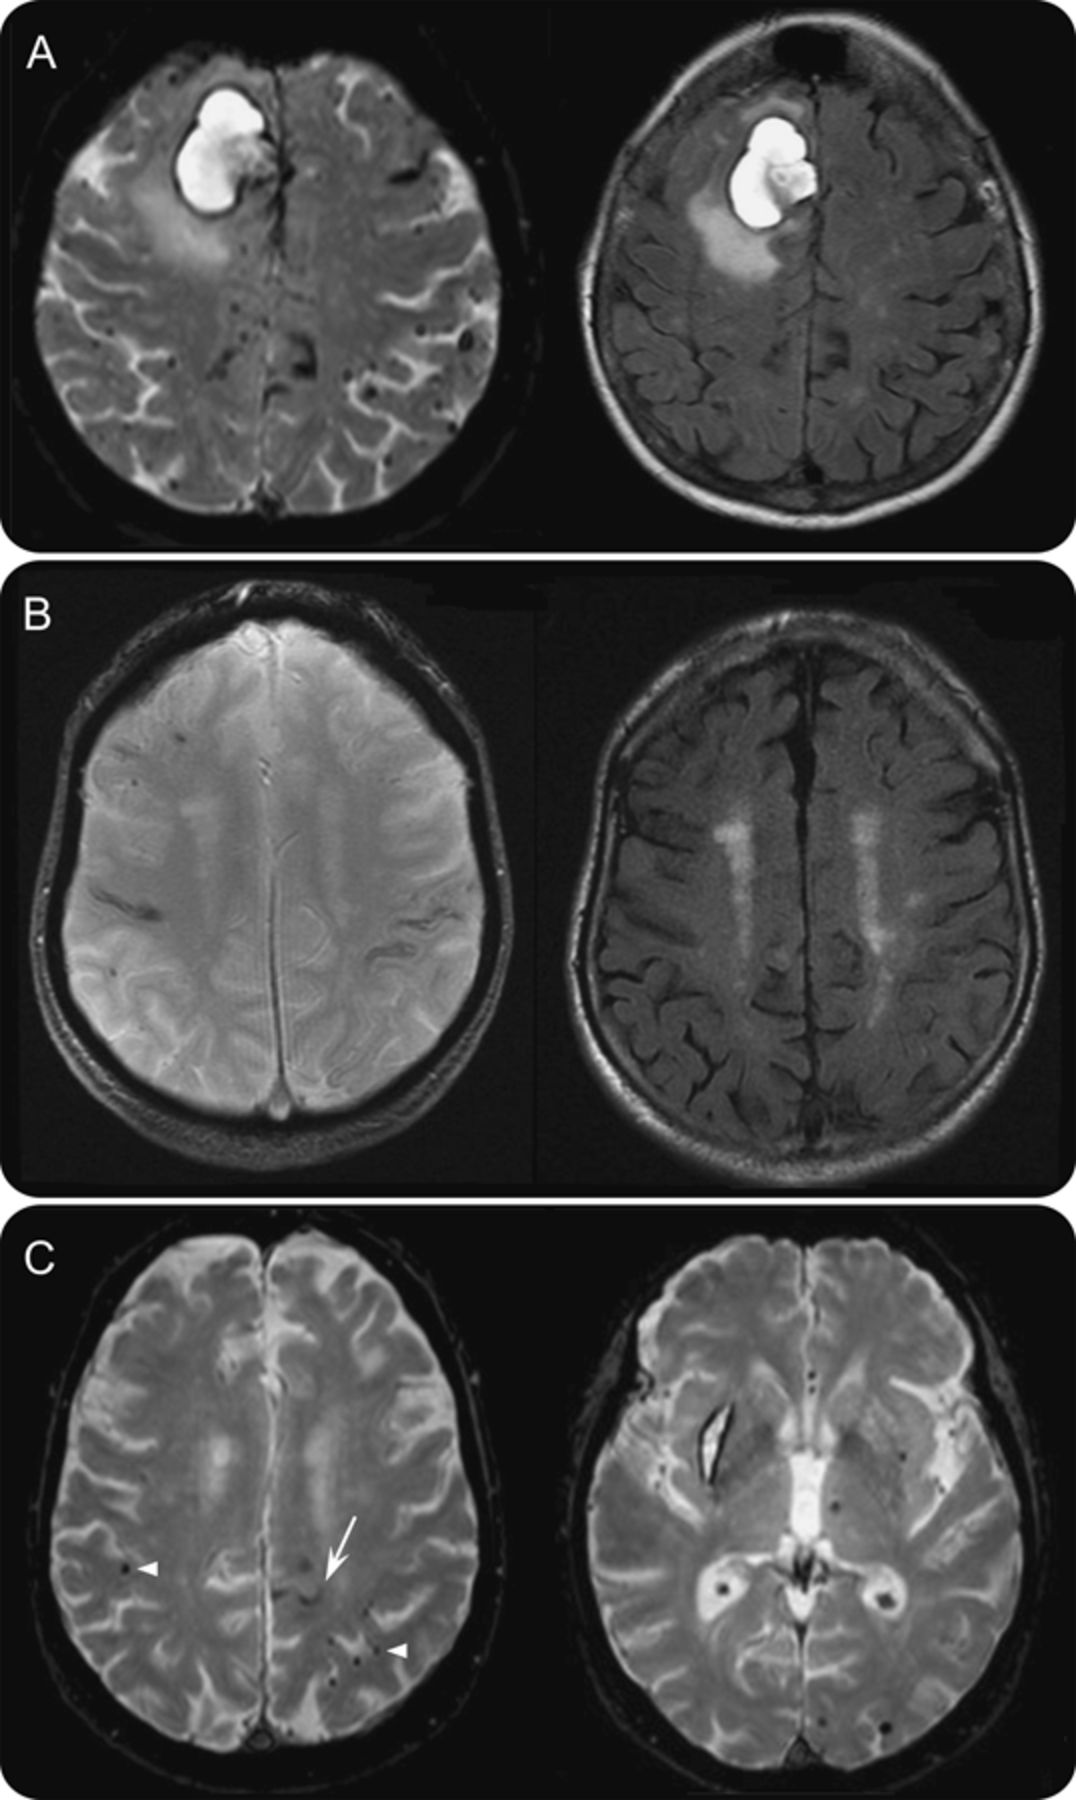

(A)患者可能脑淀粉样血管病(CAA)和急性颅内出血(我)和多焦点的右额叶皮层表面的铁尘肺(cSS)在左半球。多叶的脑microbleeds (CMBs)也在场,有时接近cSS。(B)患者可能与焦创新艺人经纪公司,双边cSS和叶的CMBs,没有我在场。(C)患者出血的混合模式(我和CMBs)不履行波士顿标准创新艺人经纪公司:注意焦点的cSS在左半球(箭头)和叶的CMBs密切附近的cSS(箭头)。天赋= fluid-attenuated反转恢复;T2 * gre = T2 *三梯度回波回忆道。

31 48患者可能的创新艺人经纪公司和cSS的慢性叶的我;cSS是侧我或双边24例(87.4%)患者和局限于同侧慢性脑叶的我只有7个患者(22.6%)(即。cSS是存在的,在大多数情况下,远离任何慢性大叶性我)。17的48名患者可能的创新艺人经纪公司和cSS(35%),没有任何证据表明慢性叶的我。代表cSS所示的例子图2。

cSS中检测出48 120 (40%;95%可信区间[CI]: 31.2% - -49.3%)患者可能的创新艺人经纪公司,相比之下,67年10 (14.9%;95%置信区间:7.4% - -25.7%)的患者一个叶的我或混合(大叶性和深度)出血,只有1的22例(4.6%)患者严格深出血(p< 0.001(趋势)表1和图1)。在单一大叶性我或混合出血组,cSS被发现在2 33(6.1%)患者单个叶的我,没有CMBs, 11例(18%)患者的第2大叶性我和深度或混合CMBs, 17和图3(18%)患者深我和叶的或混合CMBs的cSS的频率(见表格e 1详细的患者亚组)。传播cSS观察120年29 (24.2%;95%置信区间:16.8% - -32.8%)患者可能的创新艺人经纪公司,但在没有其他的89名患者没有满足原始的波士顿标准可能的创新艺人经纪公司(p< 0.001)。在单一的大叶性我或混合出血患者,cSS(10 67)总是焦点;这些患者10 cSS, 7例(70%)有叶的CMBs(表依照)。